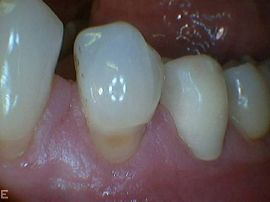

- Kariesbehandlung oder Füllungsersatz durch sorgfältig ausgearbeitete Komposit-Füllungen oder Kronen (amalgamfreie Praxis)

- Metallfreie Keramikkronen und Verblendschalen aus Porzellan (laborgefertigt), vor allem für ästhetisch wichtige Zähne